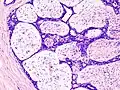

Histopathologic image of breast fibroadenoma. Core needle biopsy. Hematoxylin & eosin stain. -

Histopathologic image of breast fibroadenoma showing proliferation of intralobular stroma compressing and distorting the epithelium. H&E stain. -